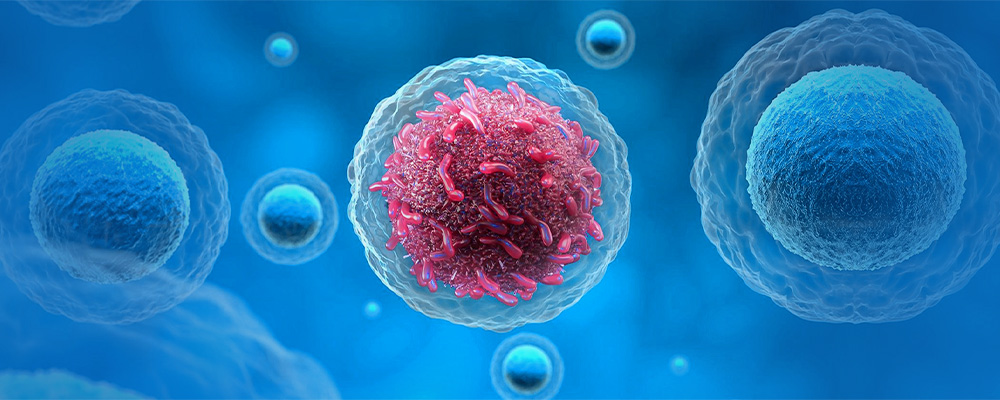

Cancer is a medical term used to refer any one of a large number of diseases, characterized by the development of abnormal cells. Diseased cells grow and divide uncontrollably. They have the ability to infiltrate and destroy normal body tissue. The disease also has the ability to spread throughout your body by the means of lymph systems and blood. Cancer cannot be specifically regarded as one disease rather it is made up of many diseases.

Cancer is caused by changes (mutations) to the DNA within cells. The DNA inside a cell contains a set of instructions guiding the cell how to grow and divide. Any disruption in the instructions may allow a cell to become cancerous.

- Allow rapid growth. As cells grow and divide more rapidly, this creates many new cells that all have that same mutation.

- Fail to stop uncontrolled cell growth. Normal cells know when to stop growing, so that you have just the right number of each type of cell. Cancer cells lose the control (tumor suppressor genes) that tell them when to stop growing. A alteration in a tumor suppressor gene allows cancer cells to continue growing.

- Biological Therapy (Immunotherapy): This therapy indirectly or directly uses the immune system of the body in order to fight cancer. This therapy also reduces the side effects that have developed due to some other cancer treatments.